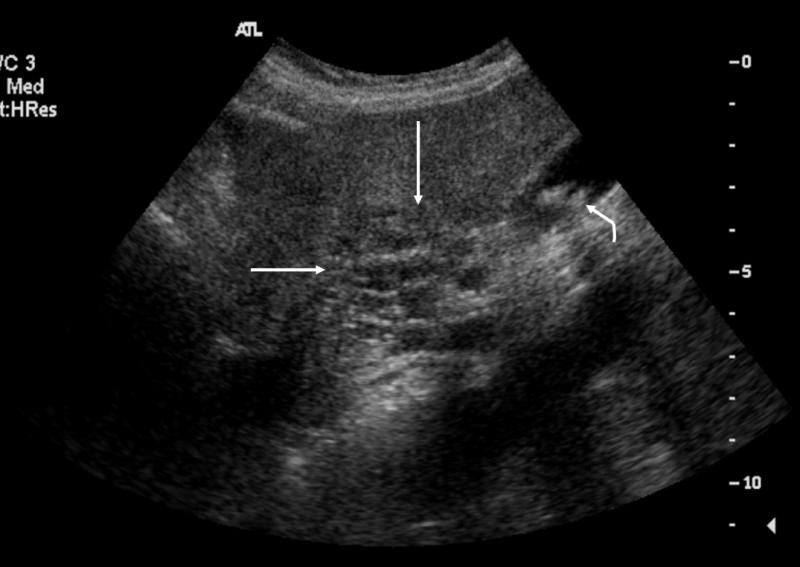

What is the sonographic appearance of Cirrhosis?

Hepatomegaly

Increased echogenicity and attenuation

Size

decrease of right lobe

Size increase of left and caudate

lobe

Nodularity

Fibrosis

Hepatospenomegaly

Ascites

Portal

hypertension

Hepatoma tumors

caudate lobe may be spared